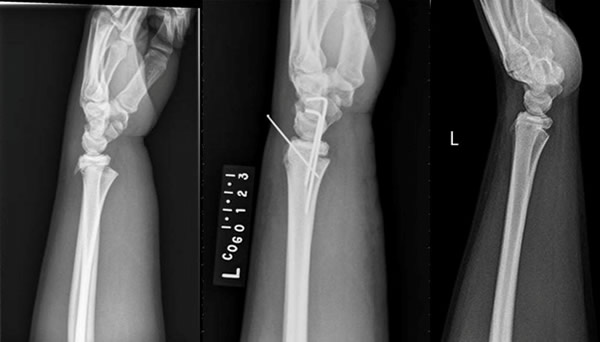

"My injury happened from a car accident. I swerved to miss a deer and rolled my truck. Initially, I was told I had a fractured left wrist and I was set up to see Dr. Jones the next morning. Dr. Jones was able to schedule me for surgery that afternoon."

Blake and his family came to see Dr. Matt Jones at Columbia Orthopaedic Group. Dr. Jones knew he'd have the put pins in his wrist to fix the fracture. It's a routine surgery that Dr. Jones has done numerous times at COG. But when he finished, Dr. Jones noticed something.

"He had what is called compartment syndrome and I had to make a decision to do something right then after we finished the surgery to pin his wrist."